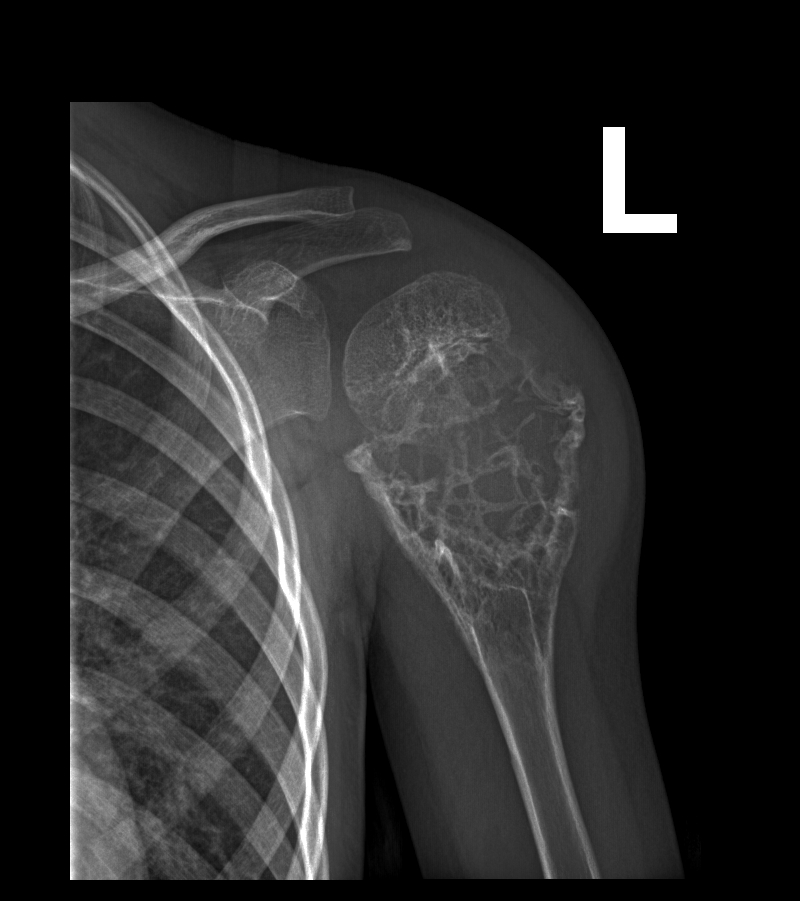

Рентгеновские снимки саркомы плечевого сустава